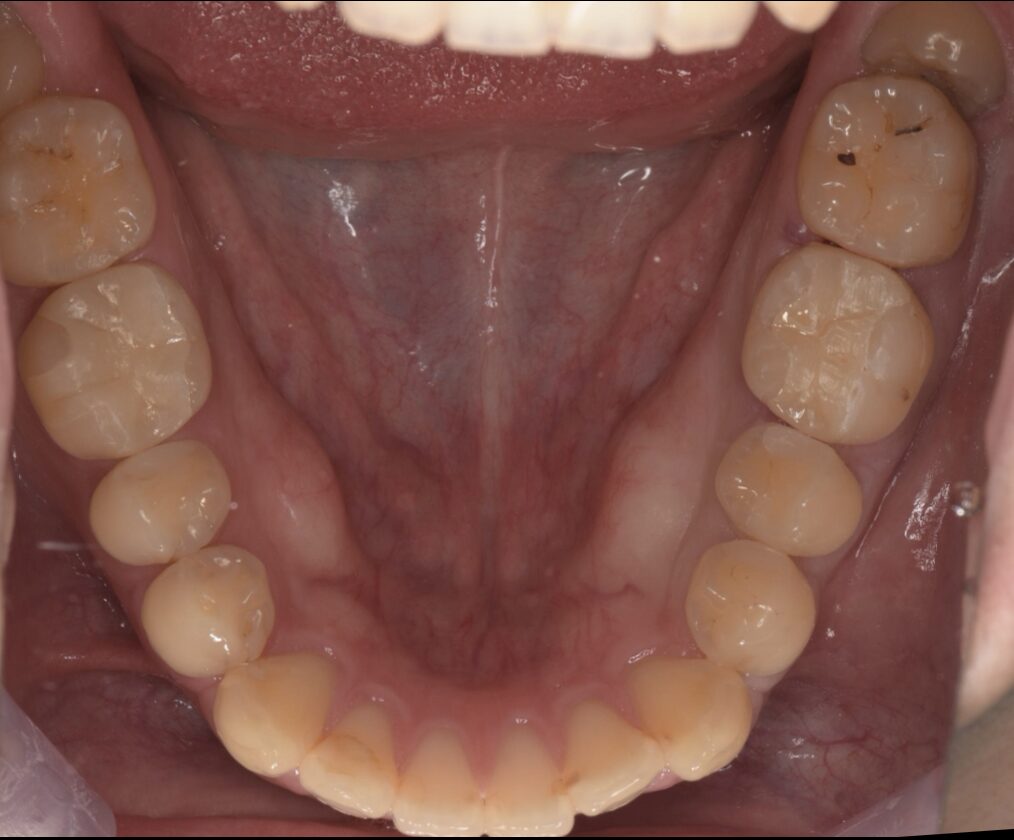

セラミック / ホワイトニング / 審美歯科

再根管治療後セラミッククラウンで治療した症例(前歯)

Before

| 治療内容 | 再根管治療、セラミッククラウン、ホワイトニング |

| 治療期間・治療回数 | 再根管治療:3回 セラミッククラウン:2回 ホワイトニング:3回 |

| 治療費用 | セラミッククラウン:170500円(税込) ホワイトニング:36300円(税込) |

| 備考 | 20代 女性 |